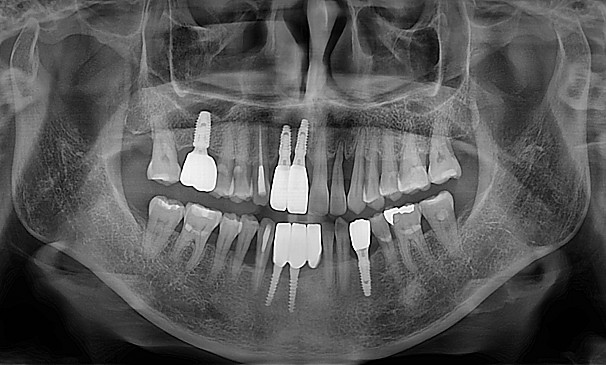

박OO님 전후사진 | 치료 기간 : 30

치료 전

치료 후